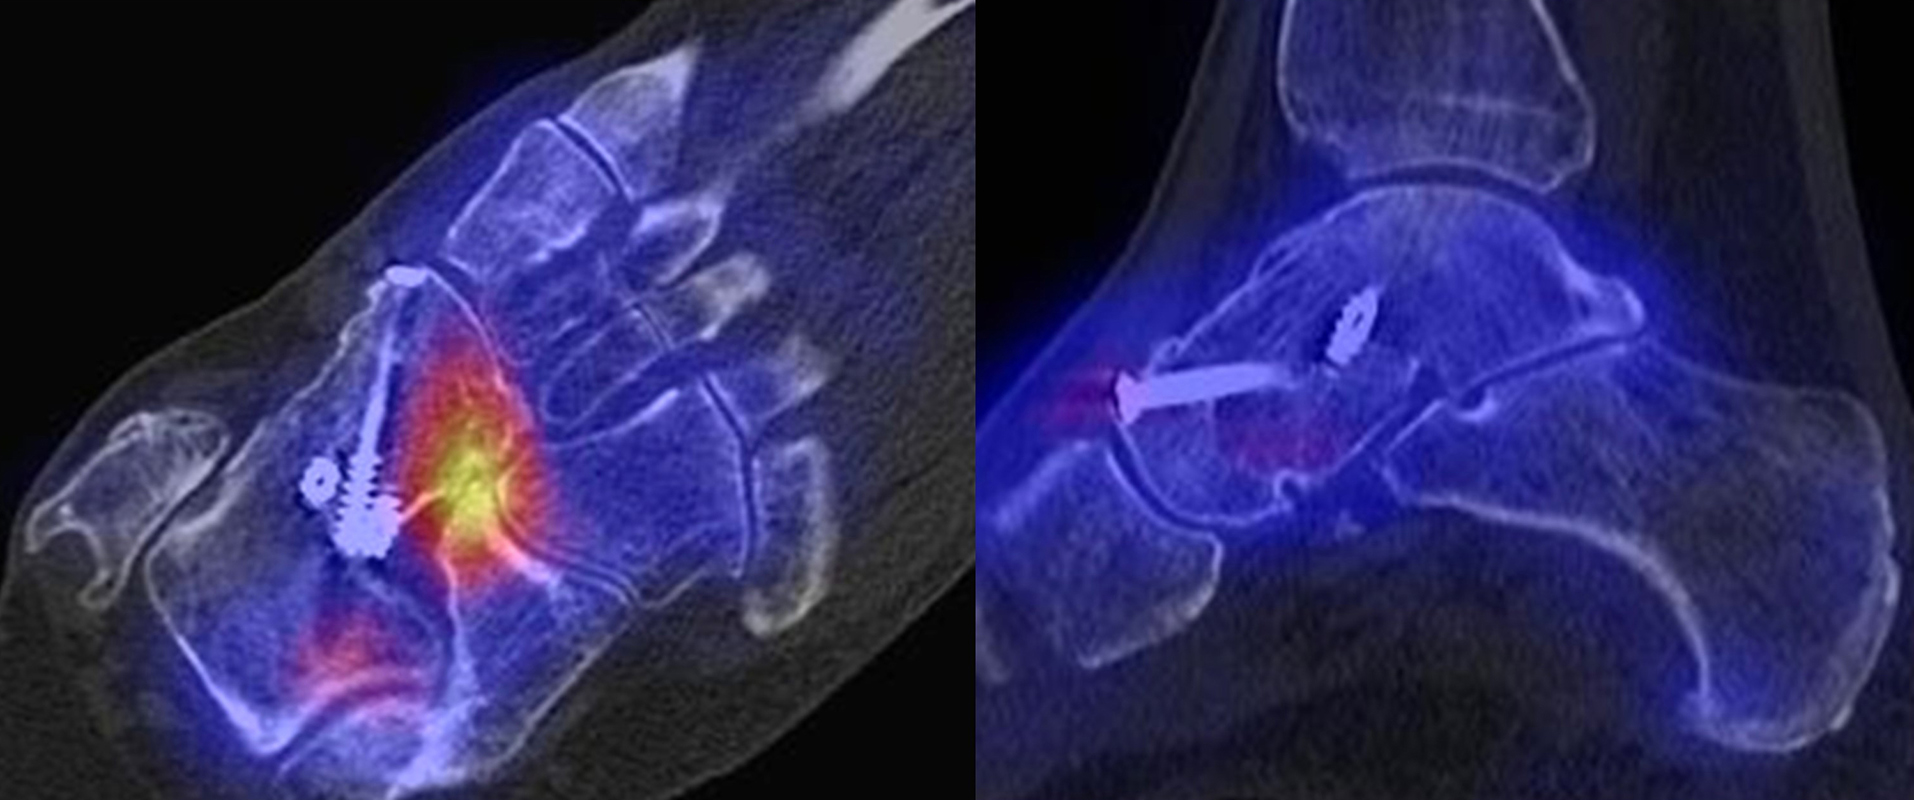

Die Abbildungen 1.5.a bis g zeigen den Infektverlauf nach operativer Korrektur einer Hallux-Valgus-Fehlstellung. Klinisch Weichteilentzündung, im MRT bei V. a. Osteomyelitis zusätzlich zur Weichteilentzündung. Das SPECT/CT wurde zur weiteren Abklärung/Bestätigung der knöchernen Beteiligung angefordert: man erkennt den gelenkbezogenen deutlich erhöhten Knochenmetabolismus im Verlauf des Naviculo-Cuneiformen-Gelenkes (Abbildung 1.5b SPECT/CT, Abbildung 1.5.c CT) und im 2. Lisfranc-Gelenk (Abbildung 1.5.d SPECT/CT sagittal auf Höhe des 2. Lisfranc-Gelenks), Abbildung 1.5.e CT sagittal), dabei CT-morphologisch verwaschene und zum Teil entkalkte subchondrale Grenzlamellen - typisch für eine begleitende (hier infektiöse) Arthritis im Rahmen der ausgedehnten Entzündung mit Osteomeyelitis.

Abbildungen 1.5.f und g: Zur Gegenüberstellung die Bilder im Rahmen der Osteomyelitis/Arthritis (Abbildung 1.5.b und c). Der Befund 1,5 Jahre später (Abbildung 1.5.f und g). Das SPECT/CT wurde zum Ausschluss/Nachweis eines Rezidivs der Osteomyelitis bei erneuten Beschwerden angefordert. Man erkennt wieder einen deutlich erhöhten Knochenmetabolismus im Verlauf des Naviculo-Cuneiformen-Gelenkes; CT-morphologisch jedoch jetzt eindeutig arthrotische Veränderungen bei im Verlauf wieder regelrechter Remineralisierung der Knochenstruktur. Im CT ist sogar im Bereich der subchondralen Geröllzysten zwischen Os naviculare und Os cuneiforme mediale ein Vakuumphänomen im Gelenkspalt zu erkennen, was eine Arthritis praktisch ausschließt. Endgültige Diagnose: postarthritische aktivierte NC-Arthrose, kein Anhalt für das Vorliegen einer Osteomyelitis oder Arthritis.